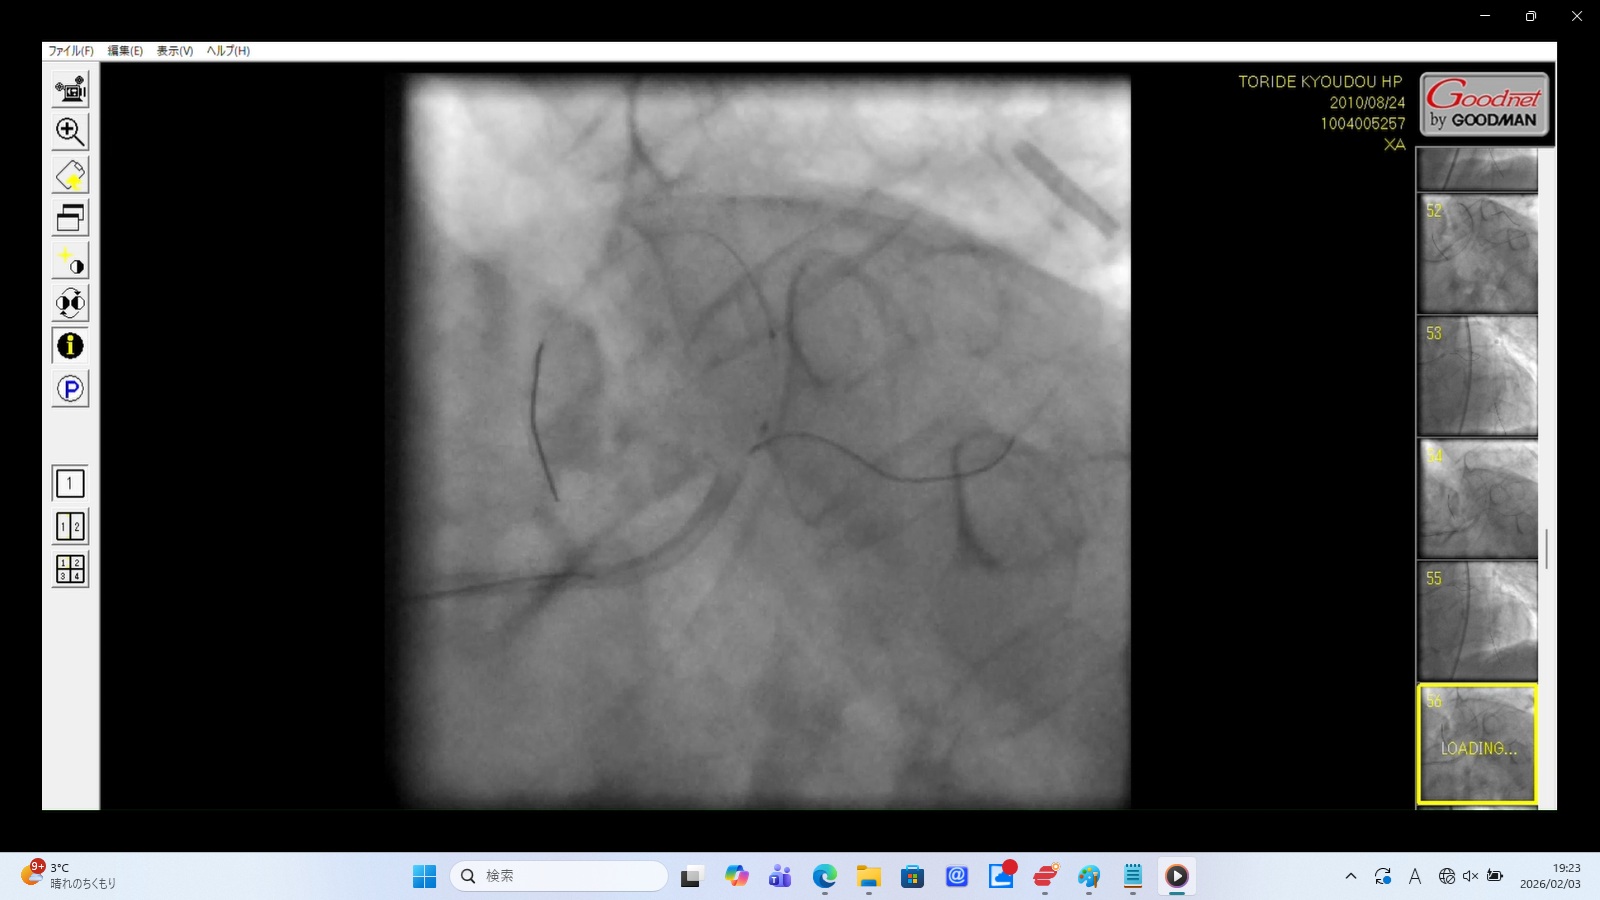

Finding: Pulsatile, cloudy movement of contrast media in the lower-left quadrant, independent of the injection timing.

Interpretation: This suggests contrast media and blood are leaking into the pericardial space, likely causing rapid cardiac tamponade.